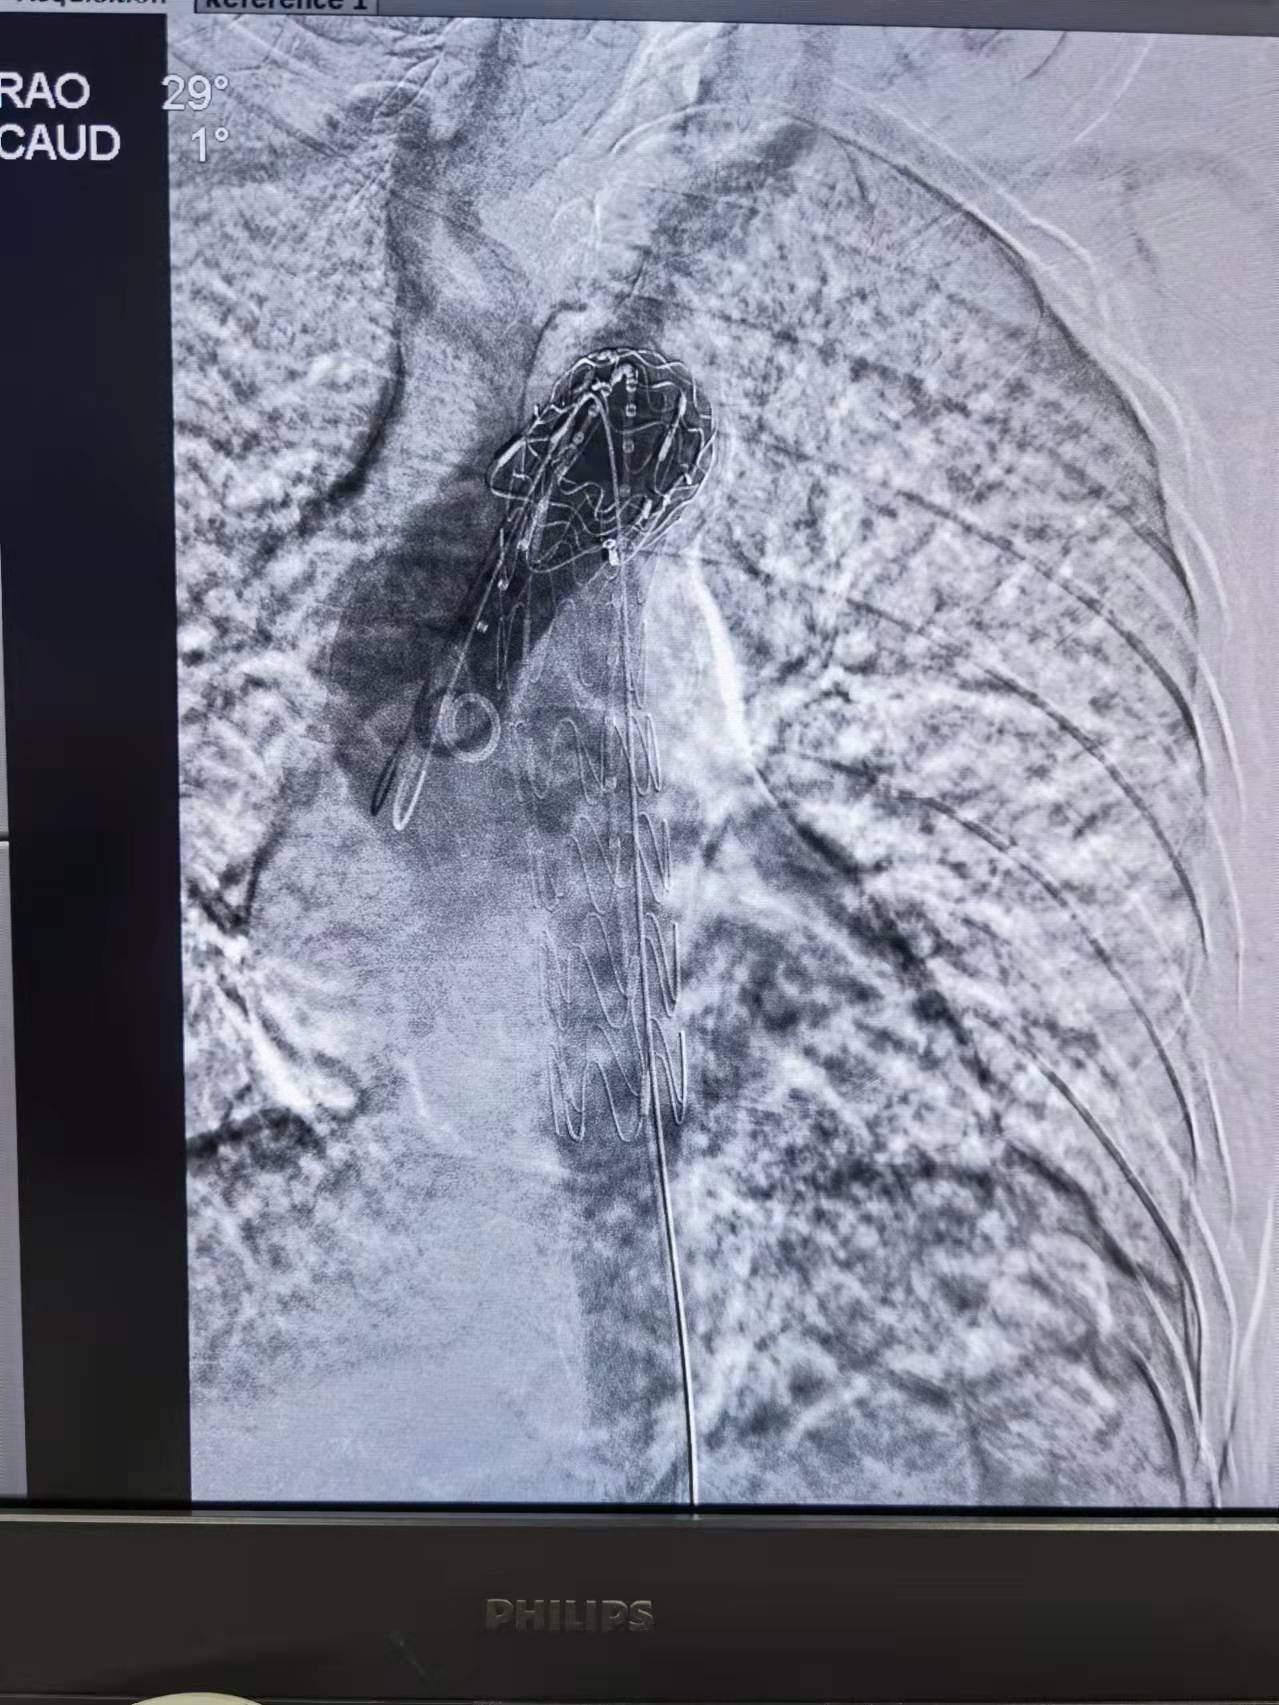

一切准备就绪后,手术按计划顺利进行,由于秦大爷的溃疡病变位于近头部供血血管附近(左锁骨下动脉),选择同时行胸主动脉支架“预开窗”技术来保留左锁骨下动脉,手术采用单纯穿刺股动脉完成,穿刺口仅仅1cm左右,避免了腹股沟切开减少了他的创伤,也节省了手术时间,2小时后手术顺利结束,秦大爷全程清醒,并没有感觉到任何疼痛。